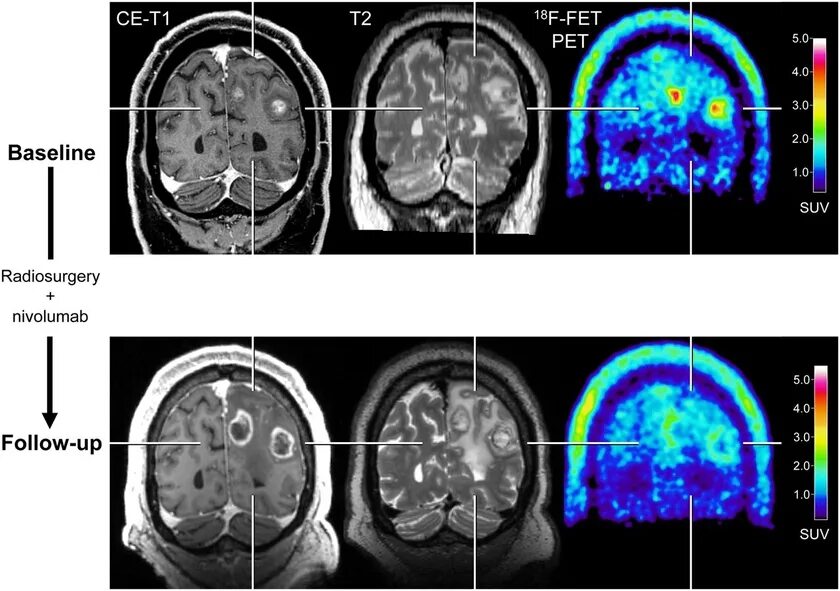

Скрининг кт